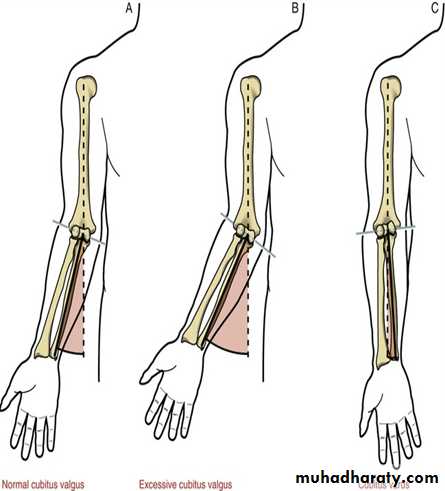

Valgus versus Varus

… In orthopedics, a varus deformity is a term for the inward angulation of the distal segment of a bone or joint.The opposite of varus is called valgus

((Which is a term for the outward angulation of the distal segment of a bone or joint.))

Cubitus valguscubitus is the Latin word for elbow and valgus means angled outward

DefinitionA deformity of the elbow that resulting in an increased carrying angle. (so that, with the arm extended at the side and the palm facing forward, the forearm and hand are held at greater than 15 degrees).

Cubitus Varus

common deformity means a deformity of a limb in which its distal part is deviated towards the midline of the body . ( extended forearm is deviated towards midline of the body).Cubitus varus is often referred to as 'Gunstock deformity', due to the crooked nature of the healing

The "opposite" condition is cubitus valgus